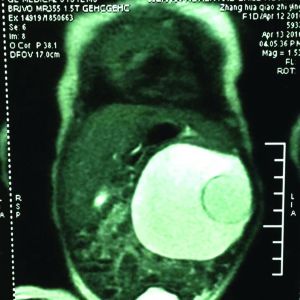

B超画面

王寿青说,临床调查显示,寄生胎的发病几率约为百万分之一。从苗苗入院时的B超,可以清楚地看到她腹中10厘米左右的囊性包块,可以看到胚胎的头、腿、脊柱。“因为胚胎已经部分坏死,留在肚子里可能会让主体感染。同时,由于胚胎与主体血管相通,会分散主体吸收的营养,随着主体长大,形成恶性肿瘤。”王寿青说,基于此,4月19日,他们给苗苗做了手术。手术时,医生们先将囊性包块中近200ml的水取出,之后又将胚胎顺利取出。